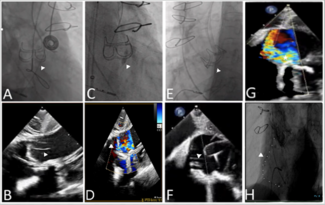

An 85-year-old man with a history of myocardial infarction and coronary bypass surgery presented with severe symptomatic aortic stenosis.

An 87-year-old man with a history of heart failure and a modified bio-Bentall Mitroflow 23-mm bioprosthesis (Sorin) was referred to our institution for critical aortic stenosis, which was confirmed by transesophageal echocardiography.